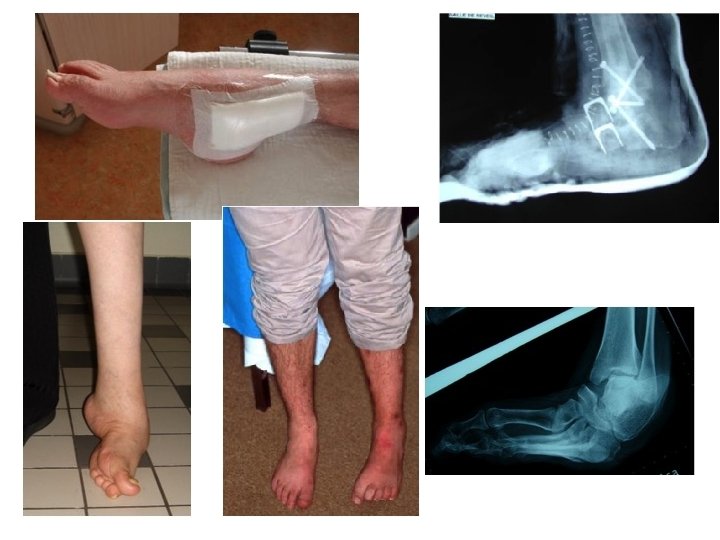

Arthrodèses

• Ostéoarthrite : long difficile, rechutes – Traitement: mêmes principes que précédemment voire amputation puis appareillage